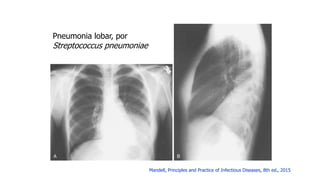

Pneumonia lobar, por

Streptococcus pneumoniae

Mandell, Principles and Practice of Infectious Diseases, 8th ed., 2015

Pneumonia lobar, por Streptococcuspneumoniae Mandell, Principles and Practice of Infectious Diseases, 8th ed., 2015